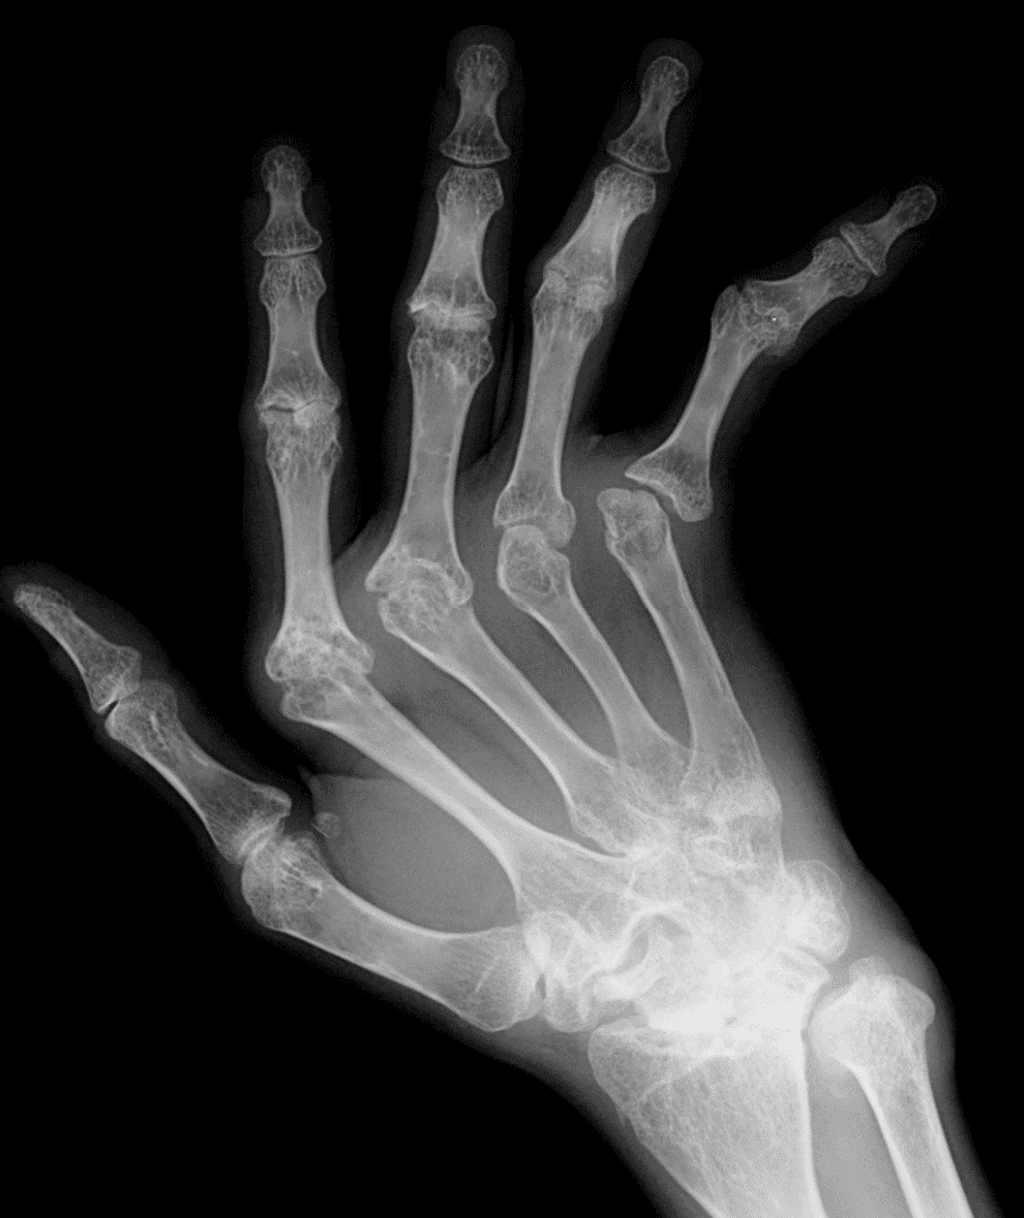

En artritis reumatoide, el patrón clásico combina tumefacción fusiforme y simétrica de partes blandas, osteopenia yuxtaarticular, erosiones marginales tempranas en cabezas metacarpianas y bases proximales de falanges, progresión a pinzamiento articular uniforme y deformidades por inestabilidad ligamentaria, como subluxación cubital en MCP. La preservación relativa de las articulaciones DIP es una pista mayor. En artritis psoriásica, por el contrario, la mineralización suele mantenerse, predominan las interfalángicas, la dactilitis aparece en cerca del 25% de los pacientes y las erosiones marginales progresan a deformidad tipo pencil-in-cup; además, la periostitis y la proliferación ósea ayudan a separarla de artritis reumatoide. La osteoartrosis erosiva, frecuente en mujeres mayores de 60 años, muestra erosiones centrales con configuración en gull-wing o seagull, con afectación predominante de DIP y respeto habitual de MCP. La artropatía por CPPD introduce otro lenguaje: condrocalcinosis en fibrocartílago triangular y ligamentos del carpo, osteofitos en gancho en la segunda y tercera cabezas metacarpianas y cambios degenerativos en una distribución no típica para osteoartrosis primaria. La gota, en cambio, combina masas de partes blandas por tofos, mineralización conservada, erosiones bien definidas con borde escleroso y márgenes colgantes; además, los cambios radiográficos pueden tardar en aparecer en promedio entre 7 y 10 años. Finalmente, el lupus eritematoso sistémico suele manifestarse con subluxaciones y deformidades reducibles sin erosiones, mientras que en esclerosis sistémica la acroosteólisis y las calcificaciones de partes blandas dominan la imagen.

El error más común es diagnosticar por un solo hallazgo aislado. Ver erosiones en DIP y concluir artritis reumatoide es una trampa clásica: en adultos, la preservación de DIP favorece mucho más ese diagnóstico que su afectación. Otro error frecuente es llamar osteoartrosis primaria a una mano con cambios degenerativos en MCP y radiocarpiana, cuando esa distribución debe hacer pensar en CPPD. También es fácil confundir erosiones centrales de osteoartrosis erosiva con erosiones marginales de artritis psoriásica, o pasar por alto que el lupus puede deformar de forma llamativa sin ser erosivo. En escenarios monoarticulares, el artículo recuerda un principio que conviene mantener siempre presente: la artritis séptica es diagnóstico de exclusión y no debe omitirse, especialmente cuando hay dolor, tumefacción y erosiones limitadas a una sola articulación. La consecuencia de estos errores no es solo semántica. Cambia el abordaje clínico, el tratamiento, el seguimiento y la urgencia diagnóstica.